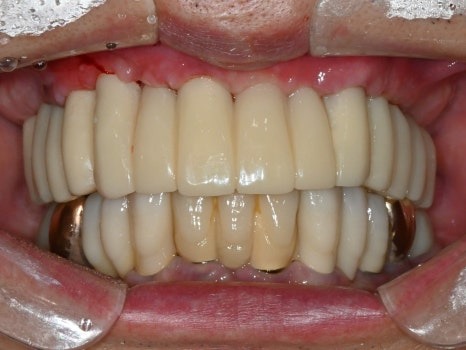

디지털 임시치아는

컴퓨터(CAD) 상에서 디자인하고

3D 프린터, 밀링 머신(CAM)으로 가공하기 때문에

손으로 빚어서 만드는 임시치아보다

훨씬 단단하고 심미적이며,

임시치아라고 해도 3개월,

길게는 1년 이상까지도 사용하면서

임플란트 치아에 적응하는 시간도 가질 수 있습니다.